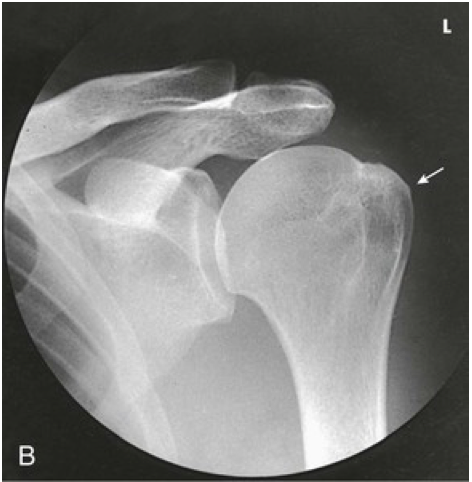

Question 3

Question

Label the image

Image:

2b92f734-ce7c-4b7f-841f-48114defa6ed (image/png)

Answer

acromion

humeral head

glenoid cavity

clavicle